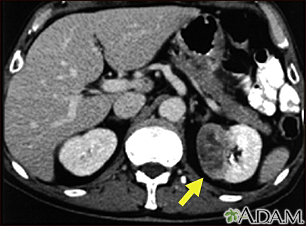

Kidney tumor - CT scan